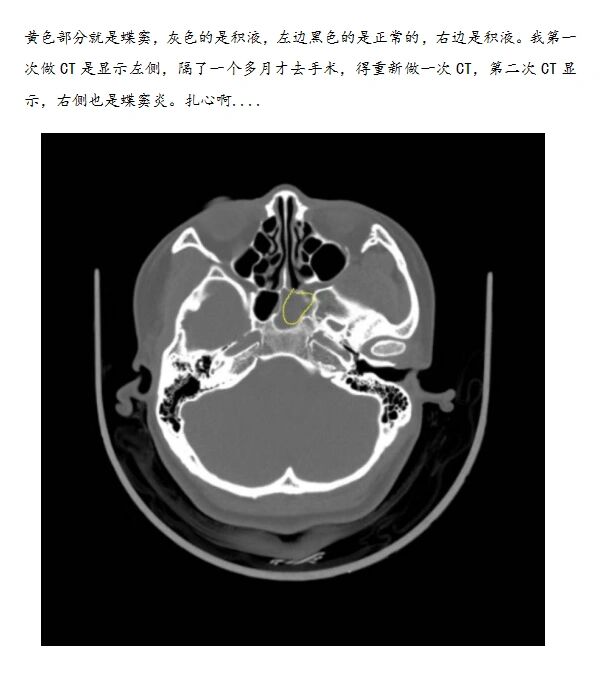

一会就失去意识了,两分钟后心跳呼吸骤停,这是送医院心肺复苏后拍的ct